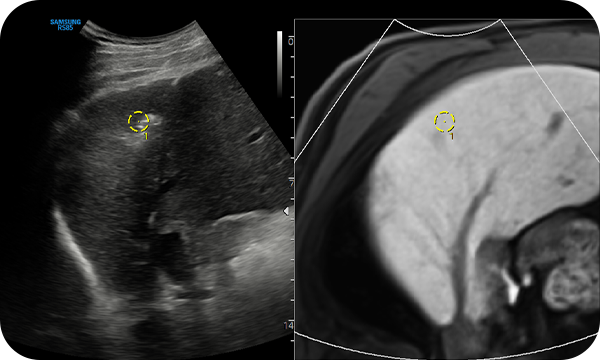

S-Fusion™ for liver enables simultaneous localization of a lesion using real-time ultrasound in conjunction with other volumetric imaging modalities. Samsung's auto registration helps quickly and precisely fuse the images, increasing efficiency and reducing procedure time. S-Fusion™ enables precise targeting during interventional and other advanced clinical procedures.

Matching Auto allows automatic initial registration by attaching external markers to the patient’s body before S-Fusion™ exam is processed, thus it helps quick and accurate exam.

Positioning Auto helps quick and efficient examination with one-step initial registration between CT/MR and ultrasound images by positioning the transducer in the patient’s pit of the stomach before patient scan.